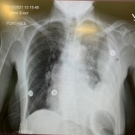

A 68-year-old woman presented to the emergency room with pleuritic left-sided chest pain associated with shortness of breath and a productive cough with clear sputum but no hemoptysis.

Vivekanand Tatineni, DO; William Christopher Baughman, MD; Keara O'Connell, MD; Vikas Jain, MD

A 63-year-old man was admitted to the emergency department with left flank pain radiating into his chest. He had initially presented to an outside hospital and was transferred after 24 hours of observation...